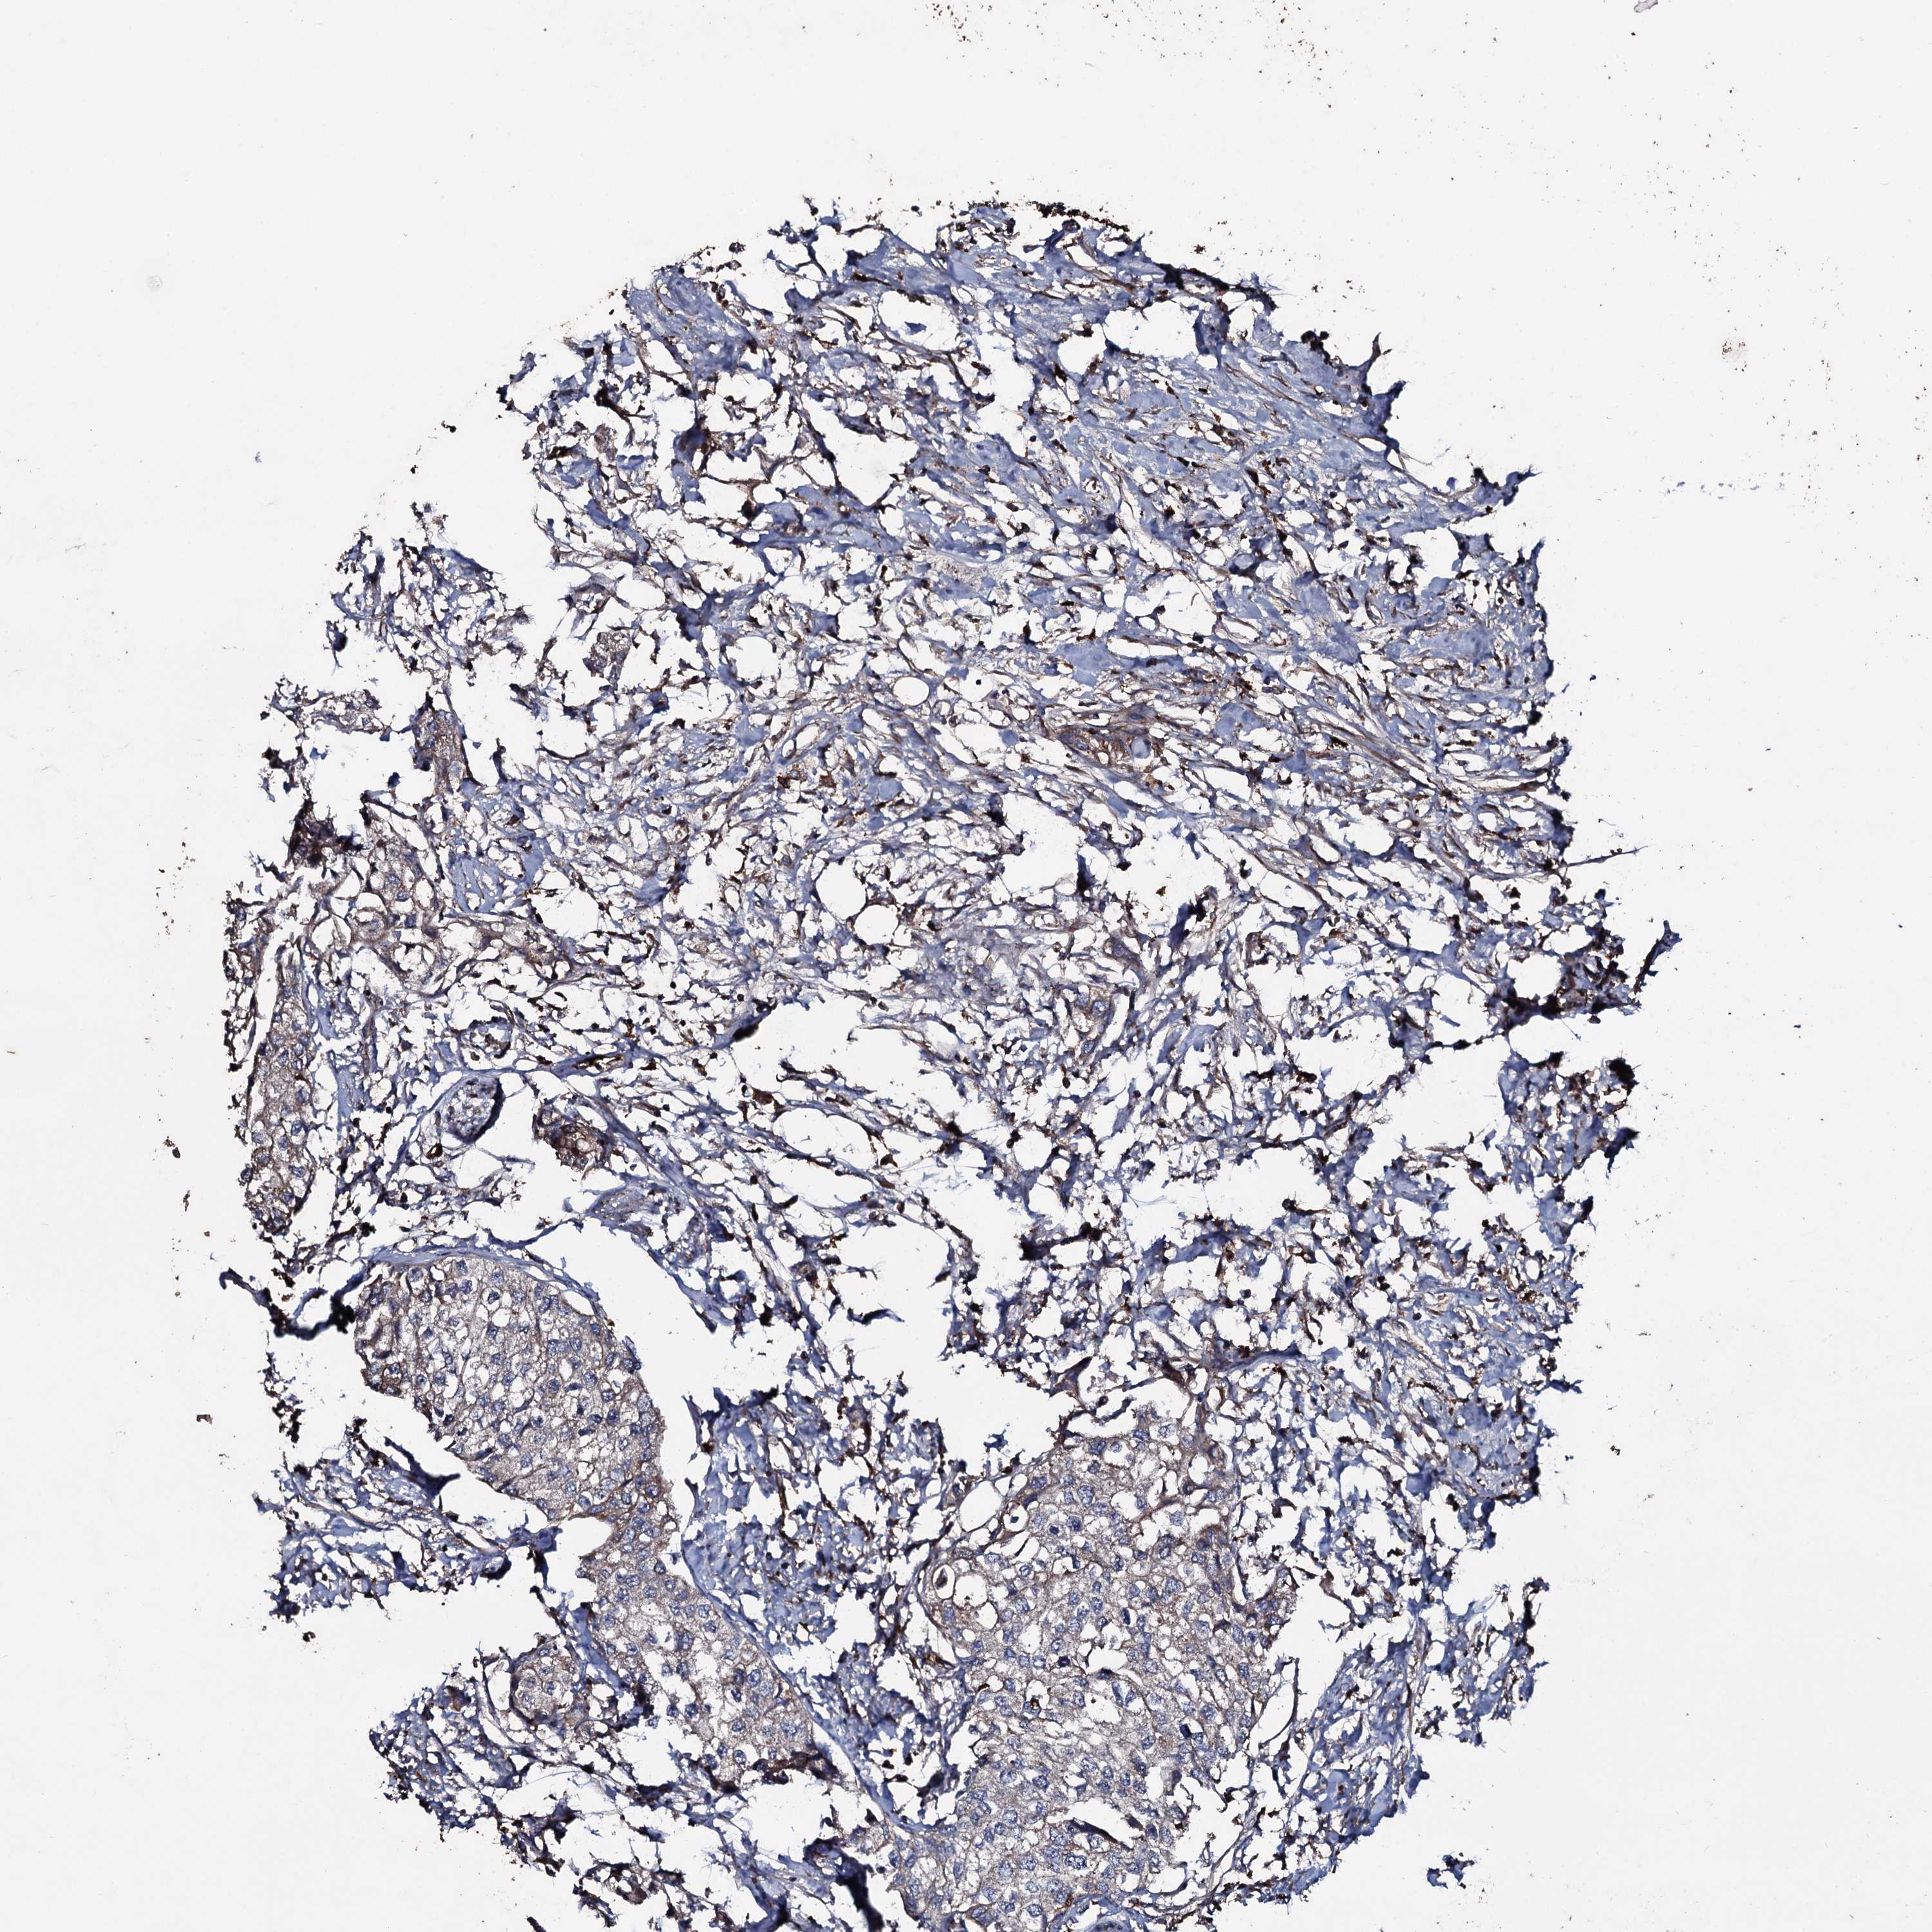

UROTHELIAL CANCER - Protein expressioni

A mouse-over function shows sample information and annotation data. Click on an image to view it in a full screen mode. Samples can be filtered based on level of antibody staining by selecting one or several of the following categories: high, medium, low and not detected. The assay and annotation is described here.

Note that samples used for immunohistochemistry by the Human Protein Atlas do not correspond to samples in the TCGA dataset.

Antibody stainingi

Antibody staining in the annotated cell types in the current human tissue is reported as not detected, low, medium, or high, based on conventional immunohistochemistry profiling in selected tissues. This score is based on the combination of the staining intensity and fraction of stained cells.

Each image is clickable and will lead to virtual microscopy that enables deeper exploration of all samples and also displays staining intensity scores, fraction scores and subcellular localization as well as patient and tissue information for each sample.

Antibody HPA041244

Staining

High

Medium

Low

Not detected

Intensity

Strong

Moderate

Weak

Negative

Quantity

>75%

75%-25%

<25%

None

Location

Nuclear

Cytoplasmic/membranous

Cytoplasmic/membranous,nuclear

Urothelial carcinoma, High grade

Urothelial carcinoma, Low grade